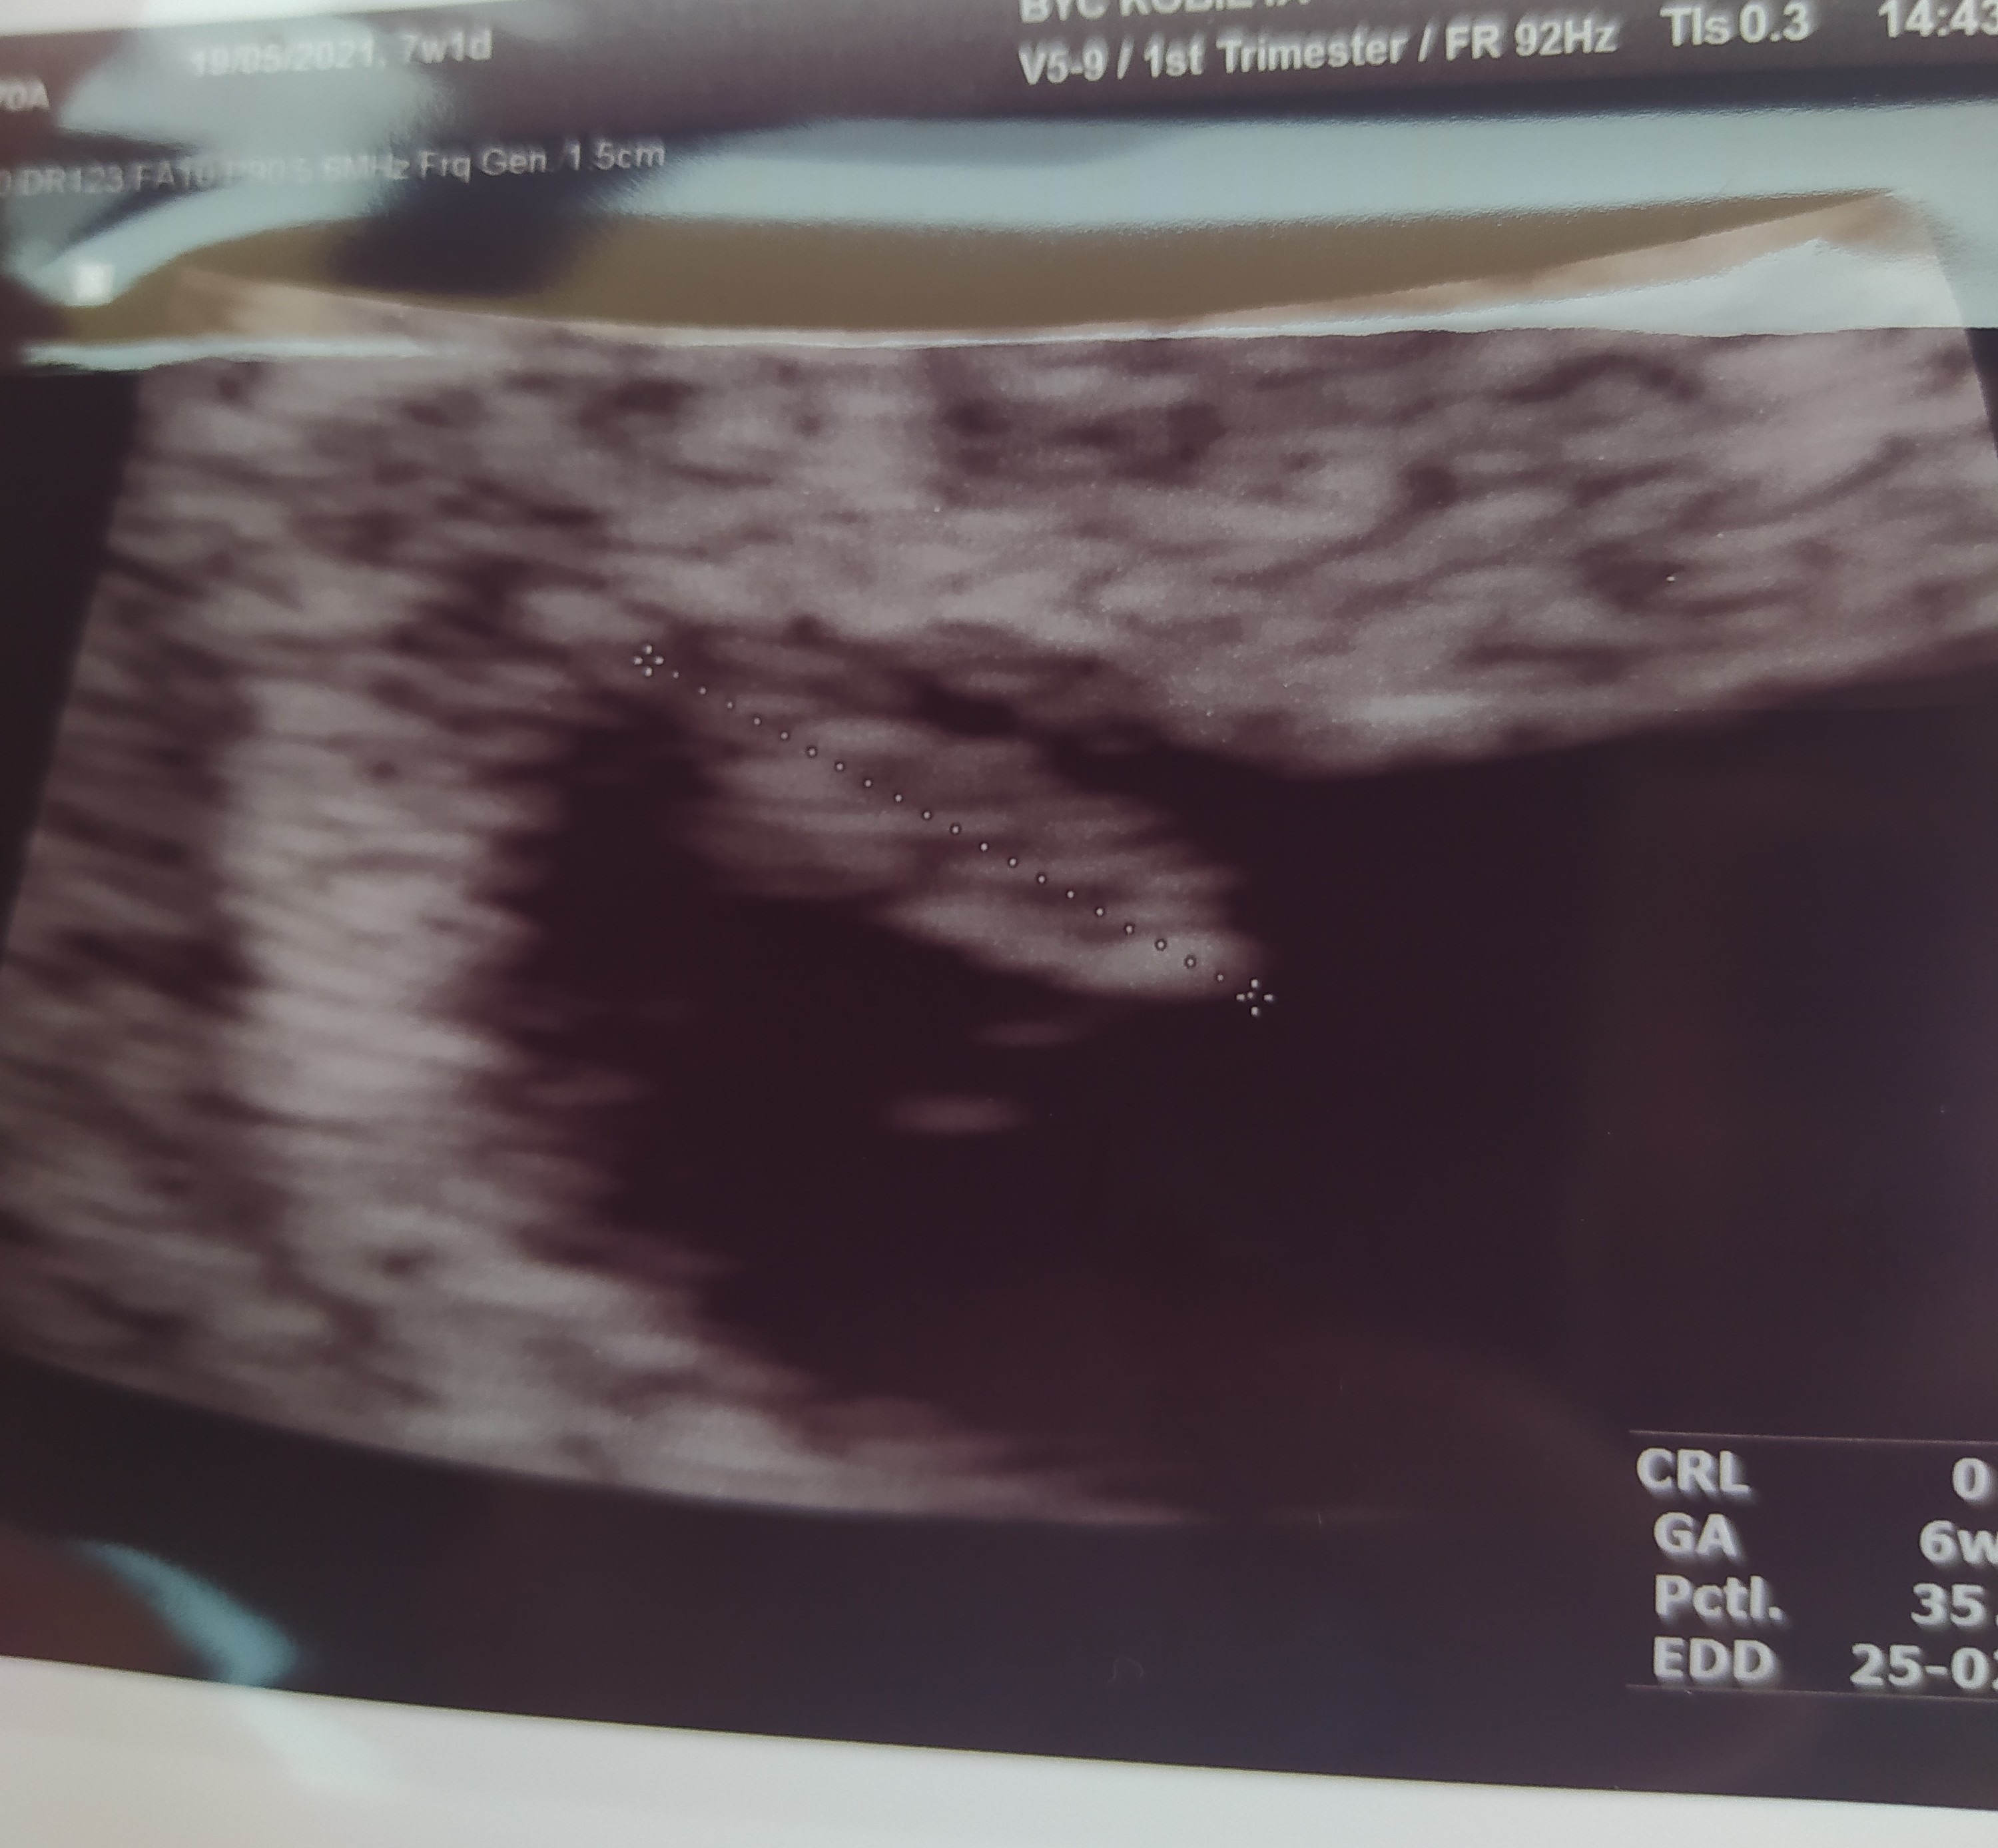

Po wizycie. 7+1. Niby wszystko ok, ale jednak coś nie tak.

Ogólnie jeśli chodzi o bejbika to rośnie i bije serduszko 😍 ale mam krwiaka 😞 dostałam Duphaston i za trzy tygodnie kolejna wizyta i zobaczymy czy się wchłonie czy co... Czy któraś z was ma podobnie?